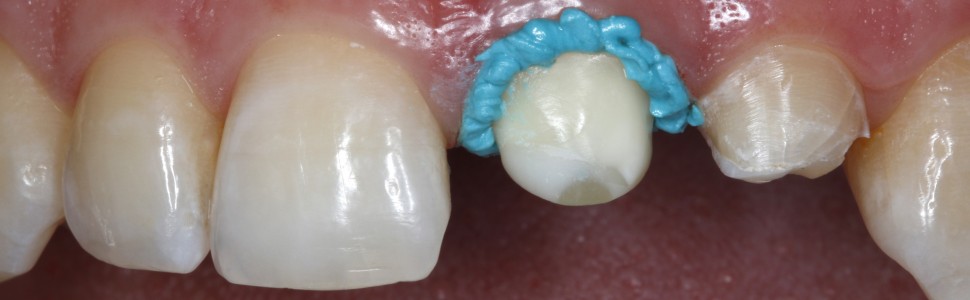

Ryc. 5. Po wprowadzeniu do szczeliny wokół zęba 21 bardzo cienkiej nici retrakcyjnej (w rozmiarze 000) wyciśnięto okrężnym ruchem pastę retrakcyjną przez bardzo cienką, zwężającą się kaniulę (pasta retrakcyjna, VOCO).

Ryc. 6. Pasta retrakcyjna jest łatwa do aplikacji, a zarazem ma dostatecznie gęstą konsystencję, aby pozwalała na dodatkowe poszerzenie szczeliny. Jednocześnie dochodzi do zatrzymania ewentualnego miejscowego krwawienia tkanek miękkich związanego z preparacją.

Ryc. 7. Ząb 21 od strony brzegu siecznego – zwraca uwagę stabilna konsystencja pasty retrakcyjnej, która utrzymuje się na miejscu po aplikacji i nie spływa.